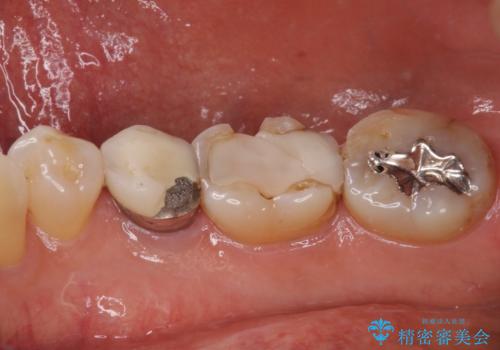

- セラミックが剥がれたり、歯質が欠けたりした奥歯を気にして来院された患者様です。

咬合力が強い方であったため、2歯をフルジルコニアクラウンにて補綴することとしました。